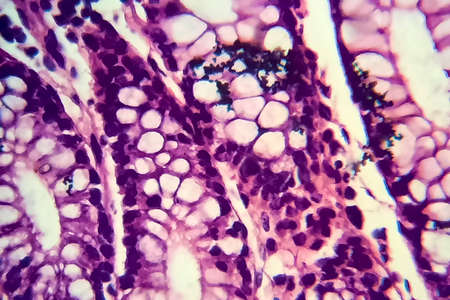

Cross section of intestinal glands (crypts of Lieberkühn) showing mucous goblet cells. Human colon.